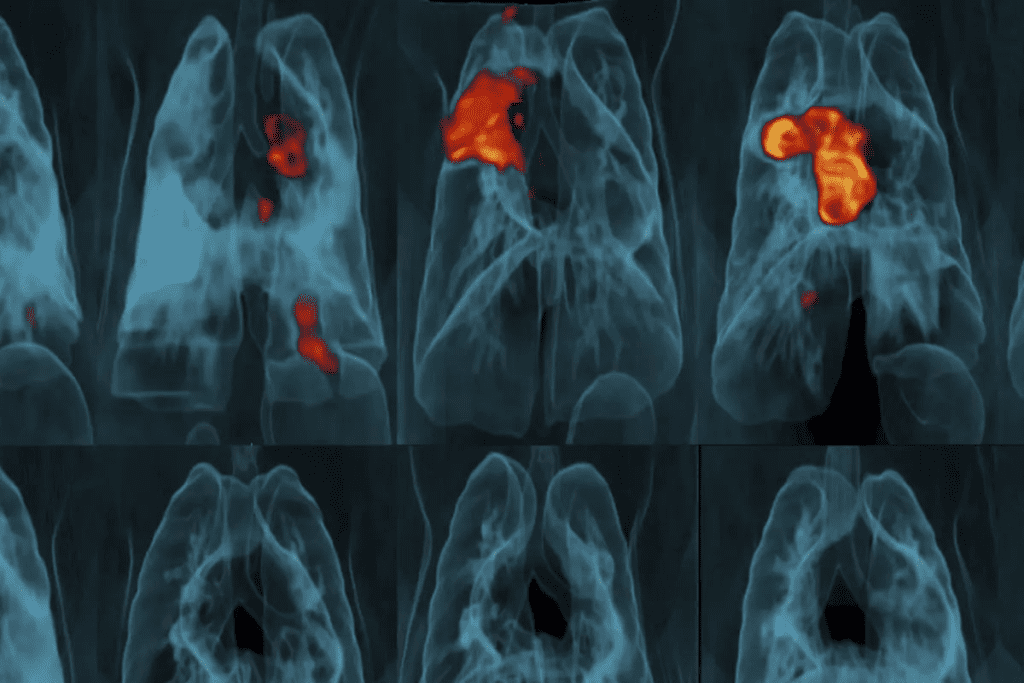

What “Hot Spots” Indicate in the Lungs

“Hot spots” in a PET scan show where the tracer is taken up more. In lung masses, hot spots can mean high activity, possibly cancer. But, not all hot spots are cancerous; they can also be inflammation or infection.

The size, intensity, and location of hot spots are important. Along with clinical information, radiologists can tell us what they mean. Their expertise helps us understand the findings.

PET Scans for Lung Cancer Staging

Accurate lung cancer staging is key, and PET scans are essential. They give us detailed info on how far cancer has spread. This info is vital for choosing the right treatment.

How PET Helps Determine Cancer Stage

PET scans are vital in finding out lung cancer’s stage. They show where cancer is active. This helps us know if it’s just in one place or has spread.

PET scans use a special tracer to find cancer. They look for areas that use more sugar than normal. This helps us stage lung cancer accurately.

Detecting Metastasis to Lymph Nodes

Checking if cancer has reached lymph nodes is important. PET scans are great at finding this out. They look at lymph nodes in the chest and elsewhere.

Identifying Distant Metastases

PET scans also find cancer in distant parts of the body. They check the whole body for cancer in organs like the liver, bones, or brain. This helps us understand how far the cancer has spread.